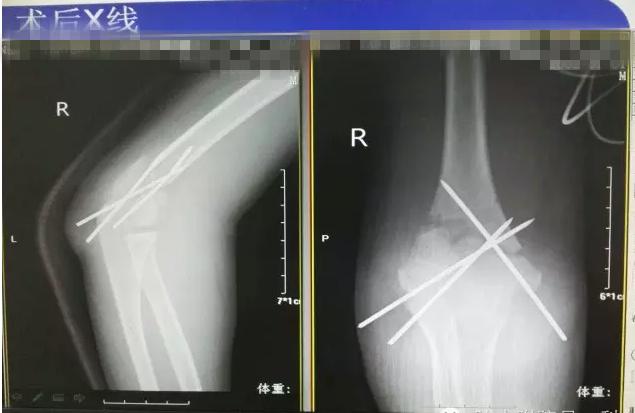

病案二:患儿谭XX,男,14岁,摔伤后右肘关节疼痛伴活动受限5小时入院。

肱骨髁上骨折闭合复位手术记录,小儿肱骨髁上骨折手术恢复的概率 诊断:Gartland III型骨折

肱骨髁上骨折闭合复位手术记录,小儿肱骨髁上骨折手术恢复的概率